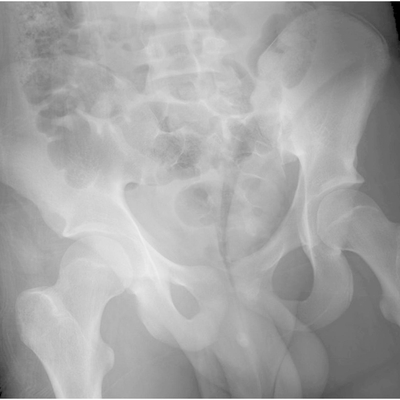

Click on an image below to view more info.